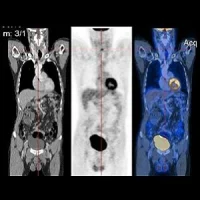

To confirm whether breast density is an independent risk factor for breast cancer, the researchers examined 3D, T1-weighted MRI breast scans done between 2007 and 2014 on 410 patients with invasive cancer in one breast, 73 patients with ductal carcinoma in situ, and 361 women with no evidence of breast cancer. The imaging technique used offers high contrast between fatty and dense glandular breast tissues, providing a more accurate measurement of breast density.

In addition, the researchers used MRI scans to assess adiposity using measurements of the fatty tissue thickness in the upper abdomen right beneath the breast. Then, investigators searched for links among breast cancer and breast density, body adiposity, and subjects' ages. Their analysis revealed strong correlation between both age and adiposity with breast cancer. However, the correlation between breast cancer and breast density alone was insignificant.